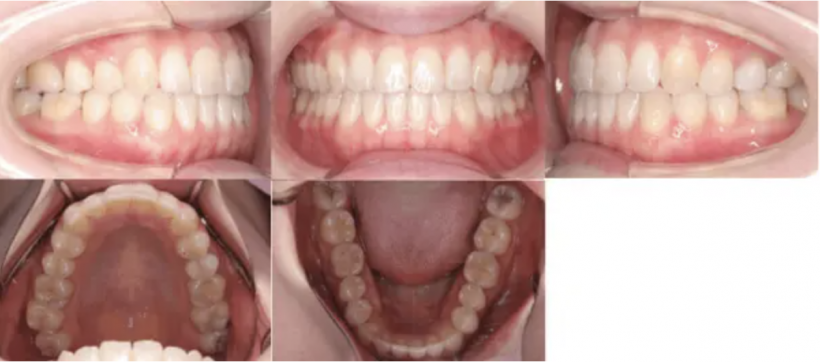

治療例②部分矯正: 23歳

【治療前】

【治療後】

治療例①②のように部分矯正によって改善された事例もありますが、部分矯正から全顎矯正に変更したことで歯並びが揃った症例もあります。